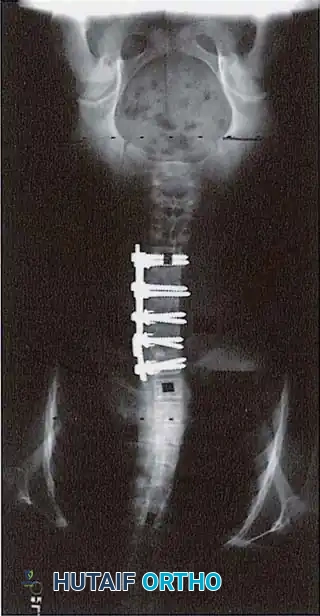

THE POSTERIOR ALTERNATIVE: PEDICLE SCREW FIXATION

Given the morbidities associated with anterior surgery, many key opinion leaders have transitioned to all-posterior approaches. Shufflebarger et al. strongly advocated for a posterior approach utilizing pedicle screw fixation and posterior column shortening for lumbar and thoracolumbar scoliosis.

The Posterior Shortening Technique

Following a wide posterior release (including complete facetectomies and removal of the ligamentum flavum), the spine is instrumented with pedicle screws and a 5.0-mm or 5.5-mm rod system.

* Advantages: This technique allows the surgeon to fuse the exact same number of levels as an anterior approach while entirely avoiding the morbidity of thoracotomy or retroperitoneal dissection.

* Outcomes: It provides excellent, rigid correction of both coronal and sagittal deformities, allowing for the restoration of physiological lumbar lordosis through posterior compression.

Potter et al. definitively compared curve correction between posterior thoracic pedicle screws and anterior single-rod instrumentation in Lenke Type 1 curves. Their findings revolutionized modern practice: Posterior pedicle screw instrumentation provided superior coronal correction, better control of thoracic torsion, and excellent spontaneous correction of uninstrumented lumbar curves. Consequently, anterior instrumentation for thoracic curves is now rarely indicated in contemporary deformity practice.